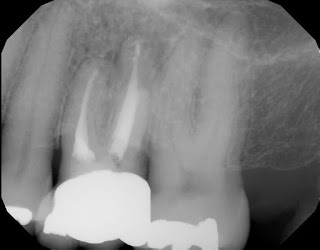

Retrofills with MTA